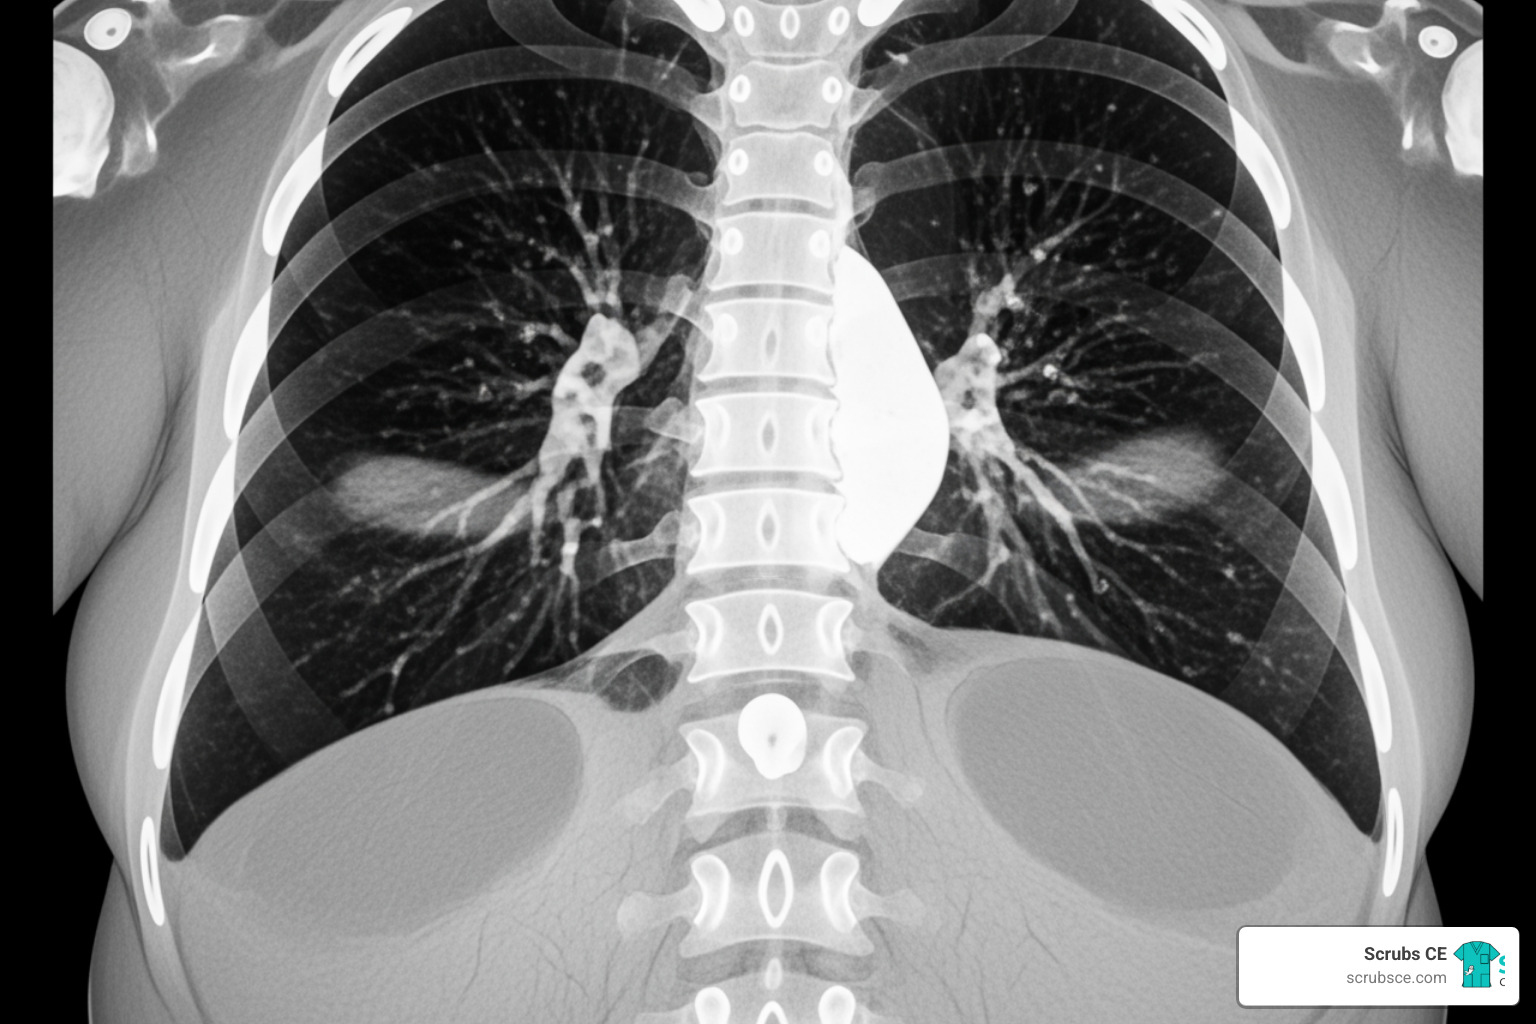

Interpreting CT scans of obese patients, especially chest CTs, requires a keen eye and an understanding of how excess weight impacts anatomy and physiology. The effects of obesity on the lungs are profound, driven by both mechanical and metabolic factors. Increased abdominal fat pushes the diaphragm upwards, leading to reduced lung volumes, particularly at the bases.

Typical chest CT findings in obese patients often include basilar atelectasis (collapsed lung tissue), which appears as wedge-shaped opacities in the lower lung lobes. We might also observe tracheal deviation, increased epicardial fat (fat surrounding the heart), and a higher risk of pulmonary embolism due to obesity-associated coagulation changes. The underlying pathological mechanisms involve decreased functional residual capacity, increased airway closure, and altered gas exchange.

However, interpreting these findings comes with potential pitfalls. A common one is misinterpreting skin folds as pneumothorax or other pathology. These folds, especially prominent in obese patients, can cast linear shadows that mimic lung collapse. The increased soft tissue can also obscure subtle findings, making detection of small nodules or early inflammatory changes more difficult. Awareness of these characteristic imaging features and potential traps is crucial for avoiding misdiagnosis. Our Body CT Secrets course offers valuable insights into interpreting complex body CT scans, including those of bariatric patients.